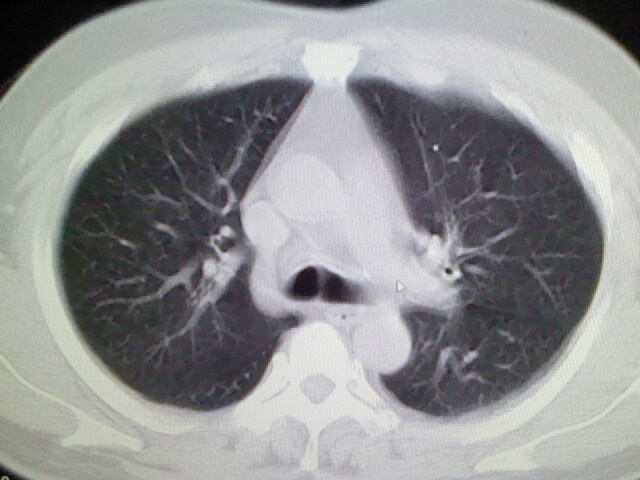

标题: CT17932:临床怀疑肺栓塞 [打印本页]

标题: CT17932:临床怀疑肺栓塞

男,34岁,自觉右侧胸痹,胸闷3天余

左肺上叶舌段少许炎症。

肺部大致正常,有可能给心脏需作个检查。